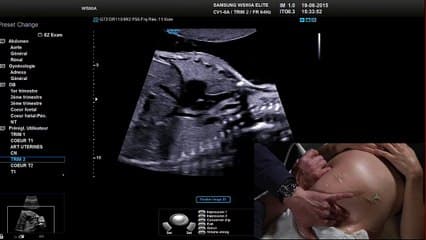

La plus grande ressource vidéo en échographie fœtale de France. Conférences, cours magistraux, démonstrations pratiques et podcasts par les experts du Collège Français d'Échographie Fœtale.

La médiathèque du Collège Français d'Échographie Fœtale (CFEF) constitue l'une des plus importantes collections de ressources vidéo dédiées à l'échographie fœtale en France. Avec plus de 3 261 vidéos, elle couvre l'ensemble des thématiques liées à la pratique échographique prénatale.

Vous y trouverez des conférences présentées lors des congrès nationaux et internationaux, des cours magistraux dispensés par des experts reconnus, des démonstrations pratiques sur des cas cliniques réels, ainsi que des podcasts et tables rondes sur les dernières avancées de la spécialité.